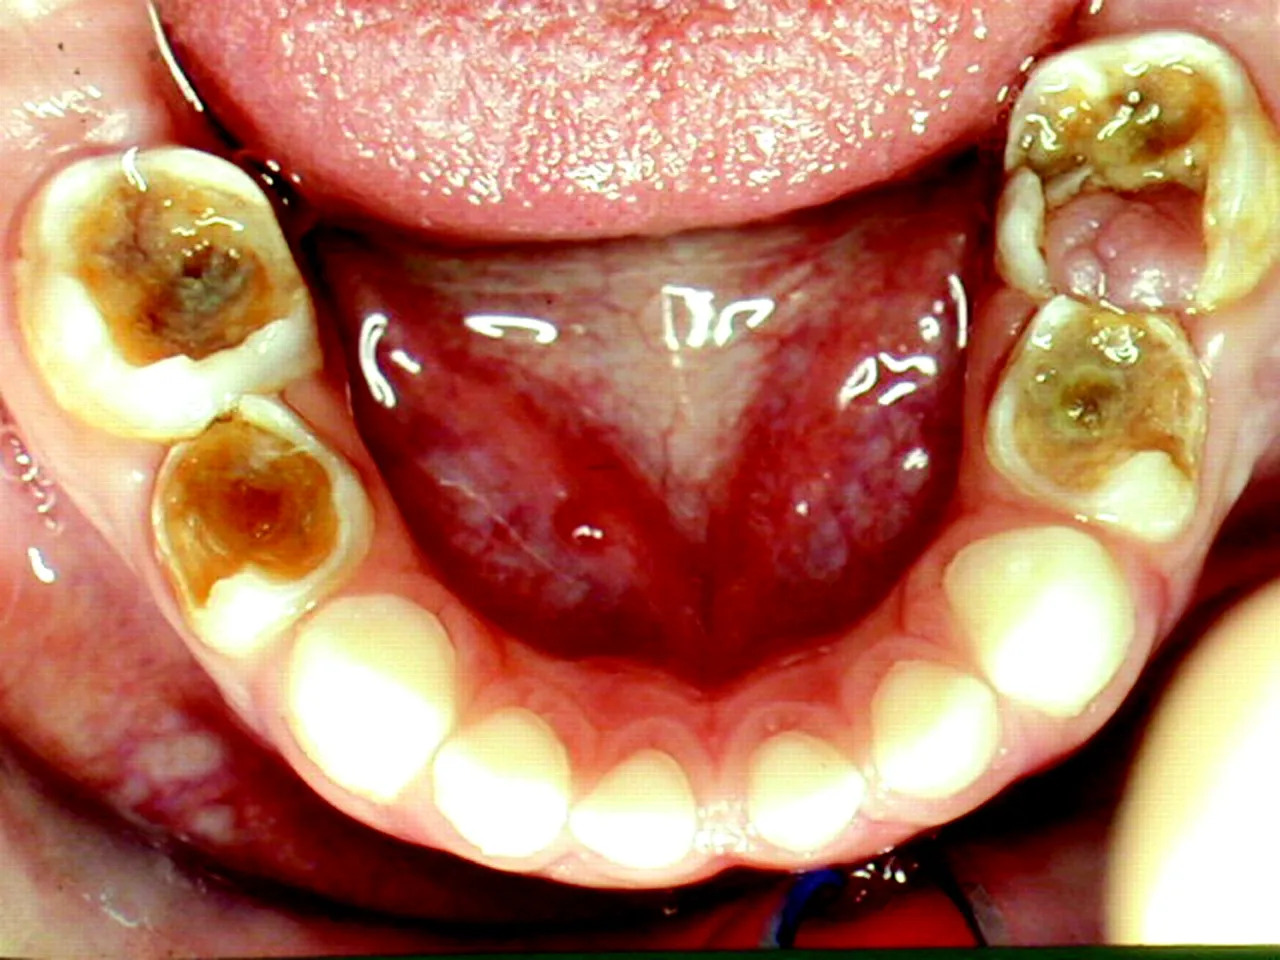

Răng sâu lồi thịt, hay còn gọi là áp xe răng – một biểu hiện của tình trạng viêm cấp tính nghiêm trọng. Phần nướu xuất hiện cục thịt dư do răng bị sâu lâu ngày không được điều trị. Cục thịt này chính là vùng niêm mạc sưng to, chảy mủ và được các chuyên gia coi là một dạng áp xe răng nghiêm trọng gây ảnh hưởng đến tủy, thậm chí có thể dẫn đến chết tủy.

Vi khuẩn từ mảng bám phá hủy lớp men răng, sau đó ăn mòn ngà răng và xâm nhập vào buồng tủy – nơi chứa dây thần kinh và mạch máu nuôi răng. Khi tủy bị viêm cấp, người bệnh sẽ đau nhức dữ dội, đặc biệt về đêm.

Nếu không điều trị kịp thời, tủy răng bị nhiễm trùng sẽ hoại tử (chết tủy). Các mô chết, vi khuẩn và bạch cầu tạo thành dịch mủ tích tụ ở chóp chân răng.

Ổ viêm nhiễm tích tụ vi khuẩn lan rộng, hình thành mảng bám, làm ố vàng và gây mất thẩm mỹ cho các răng xung quanh. Nếu không điều trị, vi khuẩn có thể phá hủy cả những răng còn khỏe mạnh.